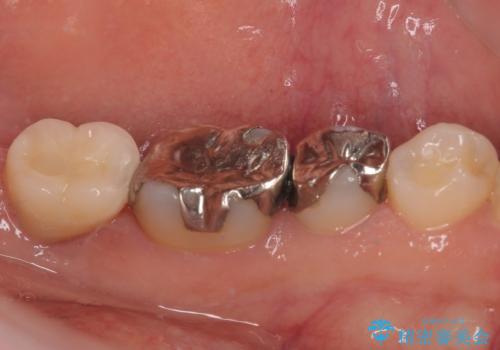

- 奥歯を抜歯してから放置しているとのことで来院された患者様です。

歯が割れて抜歯になってしまったとのことで、咬合力に抵抗できるよう、インプラントによる補綴治療を行うこととしました。

長い期間歯が欠損していた下顎奥歯に、インプラント埋入と同時に仮歯を装着すると(埋入即時荷重インプラントを行うと)、舌の付け根で仮歯を横向きに押してしまい、インプラントが脱落する危険性が高くなります。

インプラント埋入時に、装着できる状態の仮歯を用意するものの、埋入後すぐには加重させず、インプラントが無事に生着したことを確認した後に装着することで、危険を回避しつつ外科処置や痛みの少ないスムーズな治療を行うことができます。